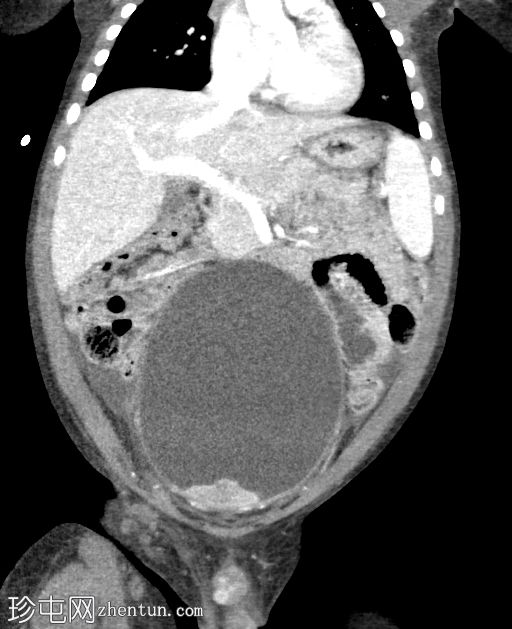

冠状位增强扫描(门静脉期)

膀胱颈下部可见一异质性强化软组织肿块,导致膀胱出口梗阻和膀胱明显囊性扩张(头尾长:19厘米)。

肿块前方与耻骨联合相邻,位于Retzius间隙内;后方与直肠和乙状结肠相邻;虽然脂肪间隙模糊,但未见明确的侵犯。

双侧输尿管肾积水,继发于膀胱出口梗阻。

CT未见明显淋巴结肿大。

肝脏、脾脏、胆囊、肾上腺和肠袢外观正常。